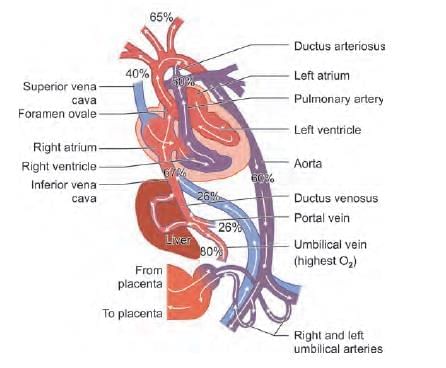

Which vessel carries deoxygenated blood back to placenta in fetal circulation? (NEET-PG 2021)